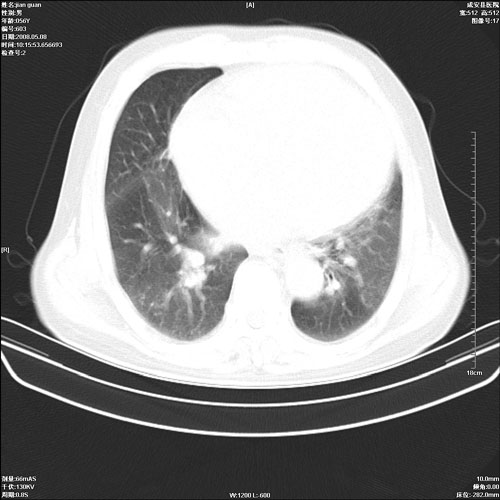

病人 男 60岁 主诉 胸闷 无明显发热 一般情况尚可。

肺结核?

两上肺陈旧性结核;慢支肺气肿、伴感染?

考虑1心功不全,肺水肿

2右上肺结核纤维性病灶、肺气肿

1.右上肺陈旧性肺结核.

2.心脏增大(以左心室增大为著),请结合b超及听诊.

1.两上肺陈旧性结核;慢支肺气肿。

2.肺门血管扩张,心脏增大,为肺心病

考虑.两上肺陈旧性结核;慢支肺气肿。肺心病

两上肺陈旧性结核,慢支肺气肿。

两上肺陈旧性结核;慢支肺气肿。肺肺间质纤维化

1.陈旧肺结核;

2.慢支肺气肿;

3.肺心病.

陈旧性肺结核,左心房扩大,左心衰竭